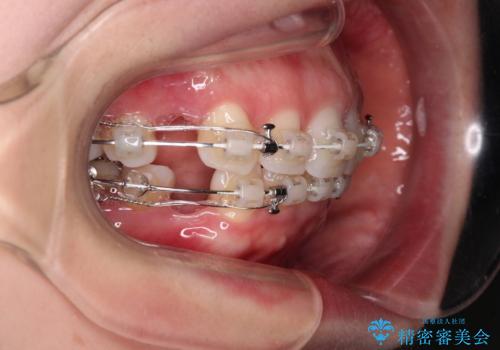

左下の大臼歯2本が顕著に舌側に傾斜しているため、まずは奥歯の咬み合わせを改善をし、その後上下左右の第1小臼歯4本を抜歯することで口元を引っ込めながら整えることとしました。

奥歯の咬み合わせ改善には1年ほどの期間と処置中の噛みにくさを強いることとなりましたが、抜歯後はスムーズに治療を完了させることができました。